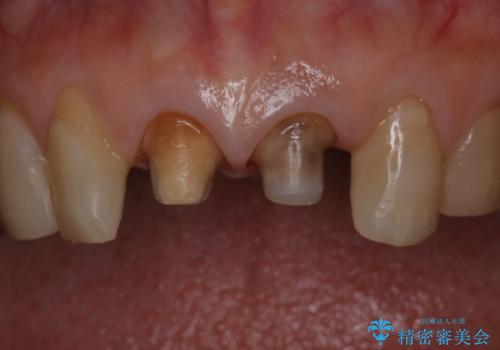

前歯の着色が気になる(失活歯)

- 前歯の着色が気になるということを主訴に来院された患者様です。

以前に、根管治療をされているみたいなのですが、そのまま放置されていてどんどん着色がひどくなり来院されました。

神経の治療をしている歯は、時間と共に色がどんどん変色していきます。

また、神経、血液供給がなくなってしまうので歯も脆くなっていってしまう為、歯が割れてしまうリスクもあります。